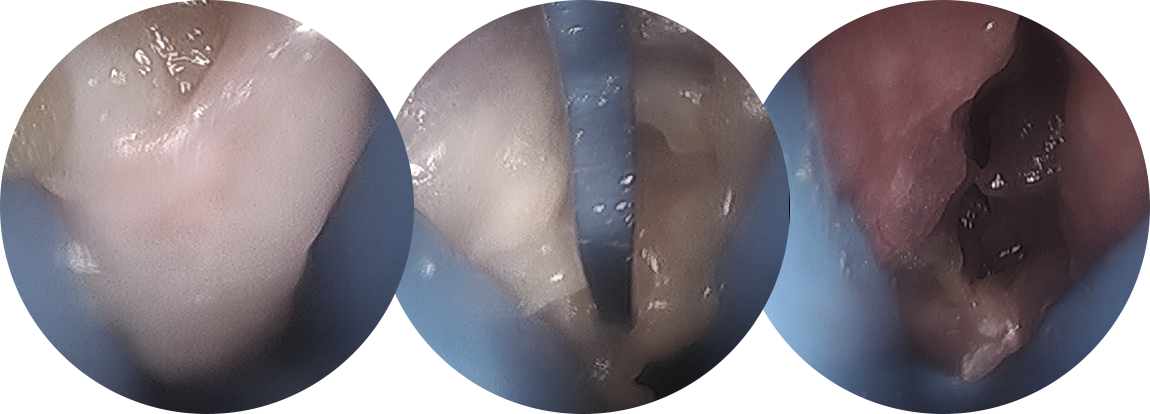

비수술적으로 치료가 되지 않는 만성 아킬레스건염에 대한 치료로, 가장 문제가 되는 부위에 최소 절개를 통해

아킬레스건 주변 염증 조직을 제거하며, 수술 후 통증이 적고 일상생활로의 회복이 빠릅니다.

* 환자에게 받은 소중한 자료입니다.

아킬레스건염이 만성 중증인 경우 다음과 같이 개방형 건활액막절제술을 통해 염증 조직 및 퇴행성 조직을 제거해줄 수 있으며,

부착성 아킬레스건염의 경우 재부착이 필요할 수도 있습니다.